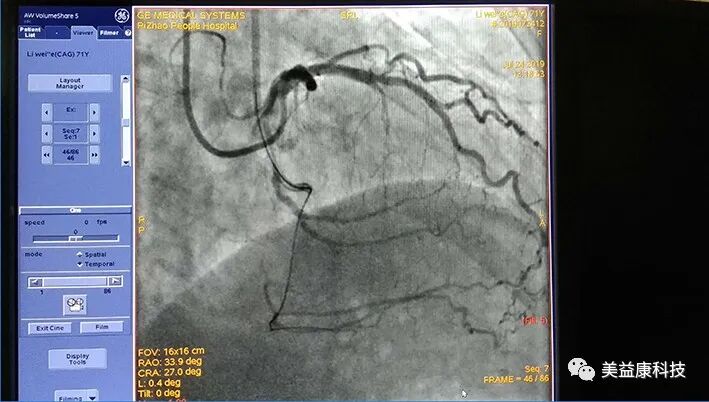

3.冠状动脉造影检查

可直接观察到冠状动脉主干及其细小分支的阻塞情况,是显示冠状动脉粥样硬化性病变最有价值的检测手段。